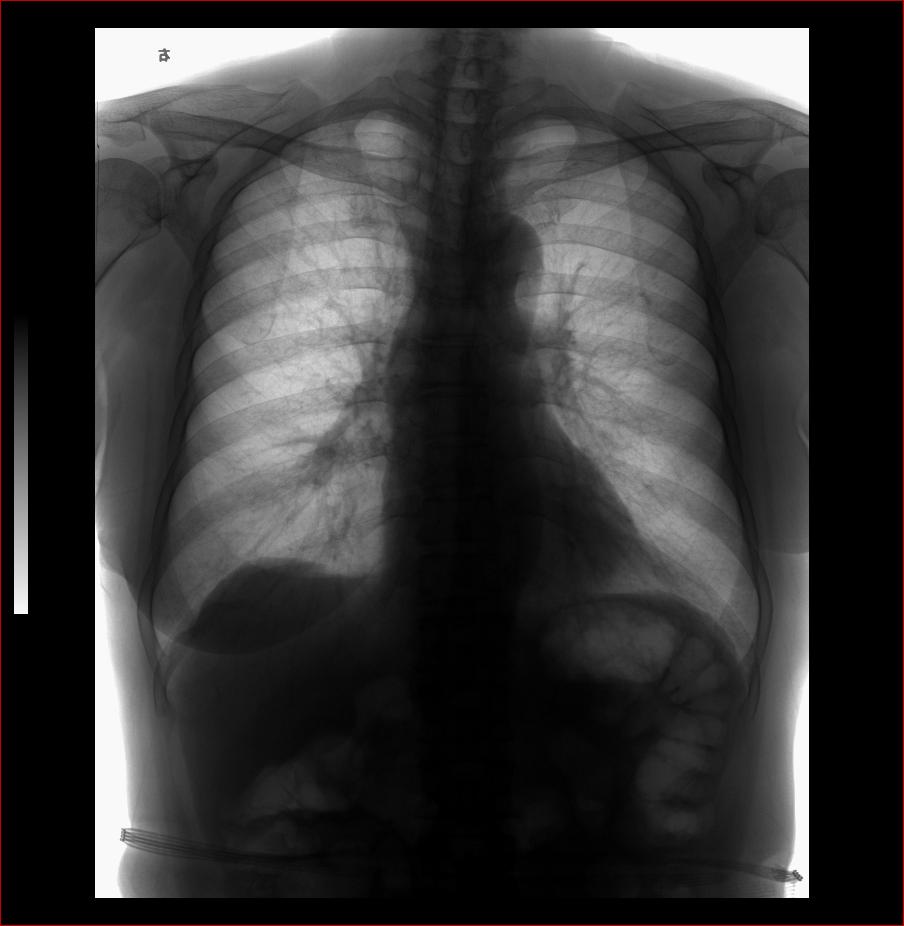

以下是引用杀毒软件在2008-3-9 20:19:00的发言:[br]如果和投照体位无关,考虑:双侧先天性高位肩胛症。

以下是引用huenhao在2008-3-9 22:45:00的发言:[br]如果和投照体位无关,考虑:双侧先天性高位肩胛症。支持